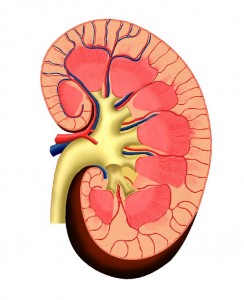

Awas, Konsumsi Vitamin C Dosis Tinggi Picu Risiko Batu Ginjal

JAKARTA - Sebuah penelitian menunjukkan orang yang mengonsumsi suplemen vitamin C setiap hari, memiliki risiko dua kali lipat menderita batu ginjal.

JAKARTA - Sebuah penelitian menunjukkan orang yang mengonsumsi suplemen vitamin C setiap hari, memiliki risiko dua kali lipat menderita batu ginjal. "Telah lama diduga bahwa vitamin C dosis tinggi dapat meningkatkan risiko batu ginjal," kata pemimpin penelitian dari Karolinska Institutet Stockholm, Laura Thomas. Suplemen biasanya mengandung sekitar 1.000 miligram (mg) vitamin C per tablet. Kebanyakan suplemen vitamin C yang dijual berisi 500 atau 1.000 mg. Ia menjelaskan beberapa komponen dari vitamin C diserap oleh tubuh dan dikeluarkan melalui urin sebagai oksalat. Oksalat adalah salah satu komponen kunci penyebab batu ginjal. Batu ginjal terdiri dari kristal kecil, yang dapat dibentuk oleh gabungan kalsium dengan oksalat. Para peneliti mengatakan tidak ada manfaat yang jelas dari mengkonsumsi vitamin C dosis tinggi. Namun, Laura menegaskan tubuh manusia tetap membutuhkan banyak vitamin C yang bisa didapat dari buah-buahan dan sayuran. Segelas jus jeruk segar mengandung hanya sekitar 120 mg vitamin C. Antioksidan yang terkandung dalam buah dan sayur sangat penting bagi kesehatan tulang dan otot. "Vitamin C merupakan bagian penting dari diet yang sehat," kata Laura, seperti yang dikutip dari Daily Mail. Laura menekankan bahwa efek vitamin C terhadap risiko batu ginjal, bergantung pada dosis dan kombinasi nutrisi yang dikonsumsi. (antara/ija)